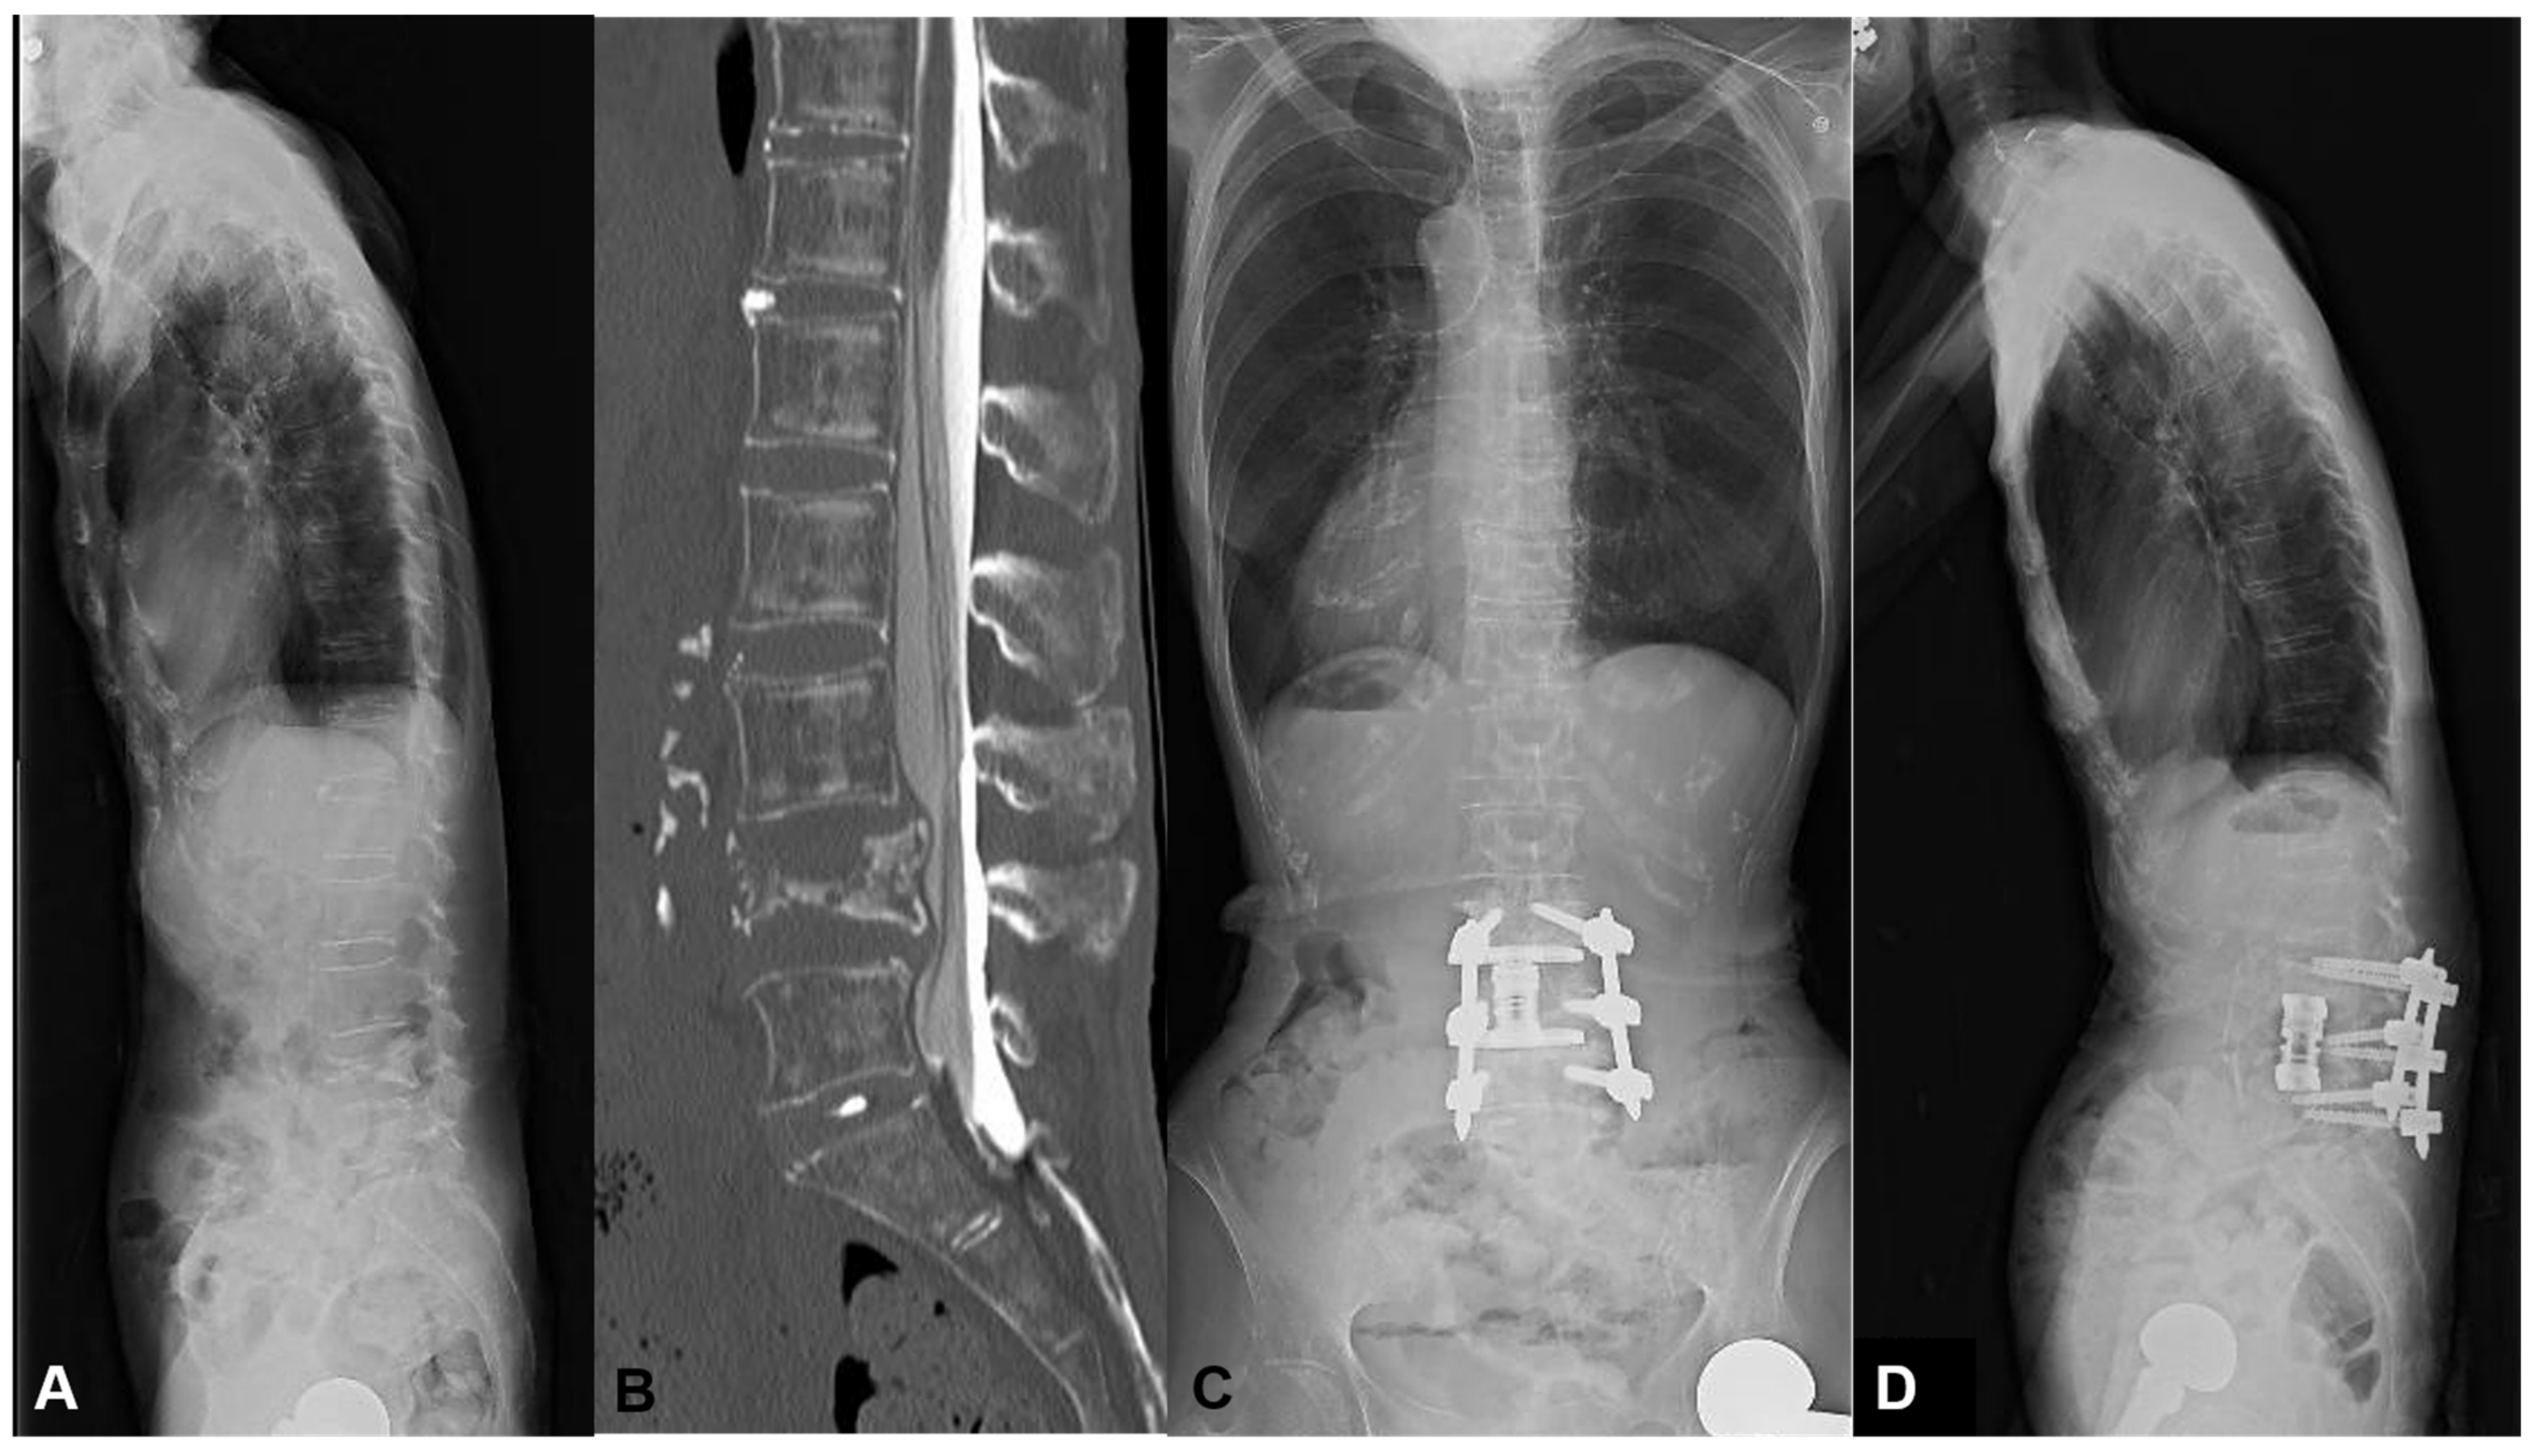

3.1.1. Case 1: 84 Years Old, Female, L1 Vertebral Collapse

She revealed severe motor weakness of right quadriceps, drop foot, and gait disturbance preoperatively. The L1 MIS corpectomy, artificial body replacement, and L2/3 XLIF were performed followed by PPS fixation. The local kyphosis of 24 degrees was corrected to 0 degrees postoperatively. Even with a high PI of 66 degrees, no mechanical complication occurred with the enhancement of the fixation level (Figure 4). The patient became ambulatory with the recovery of motor weakness.

Figure 4.

An 84-year-old female suffering from L1 vertebral collapse. The L1 MIS corpectomy, artificial body replacement, and L2/3 XLIF were performed followed by PPS fixation. The patient became ambulatory, and motor weakness recovered without mechanical complications. (A) Preoperative lateral X-ray, (B) Preoperative myelogram CT, (C) Standing AP X-ray at one year postoperatively, (D) Standing lateral X-ray at one year postoperatively.

This case was a typical example of thoracolumbar OVF with preoperative high mismatch. When the short-segment fusion was conducted, there was a very high risk for MC such as DJK.